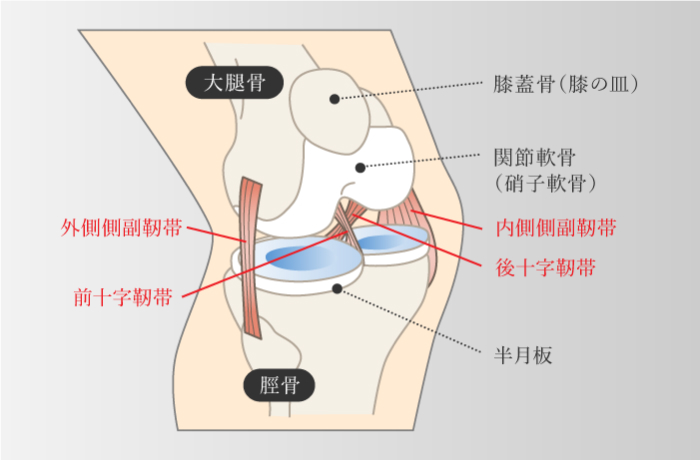

変形性膝関節症

-

関節軟骨の老化が原因になることが多く、肥満なども関与している。また骨折、靱帯や半月板損傷などの外傷、化膿性関節炎などの感染の後遺症としても発症する可能性がある。 関節軟骨が年齢とともに弾力性を失い、使い過ぎることによってすり減り、関節が変形する。

半月板損傷

-

半月板は大腿骨と脛骨の間の三日月型をした組織で、膝関節のクッションの役割を果たしている。ジャンプ時の着地や方向転換など荷重された状態で膝を強く捻ったり、キック動作で膝を急激に伸ばす動作やその反復で損傷する。

膝の靭帯損傷

前十字靭帯・後十字靭帯・内側側副靭帯・外側側副靭帯

膝の靭帯損傷

前十字靭帯・後十字靭帯・内側側副靭帯・外側側副靭帯

-

膝関節は、前十字靭帯、後十字靭帯、内側側副靭帯、外側側副靭帯の4本と2種類の軟骨で構成されている。上記4本の靭帯損傷はスポーツや外傷など、膝に強い力がかかった場合に起こり、その力の方向によって損傷する靭帯が異なる。